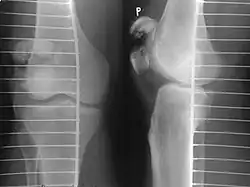

A fracture of the patella seen on a lateral view